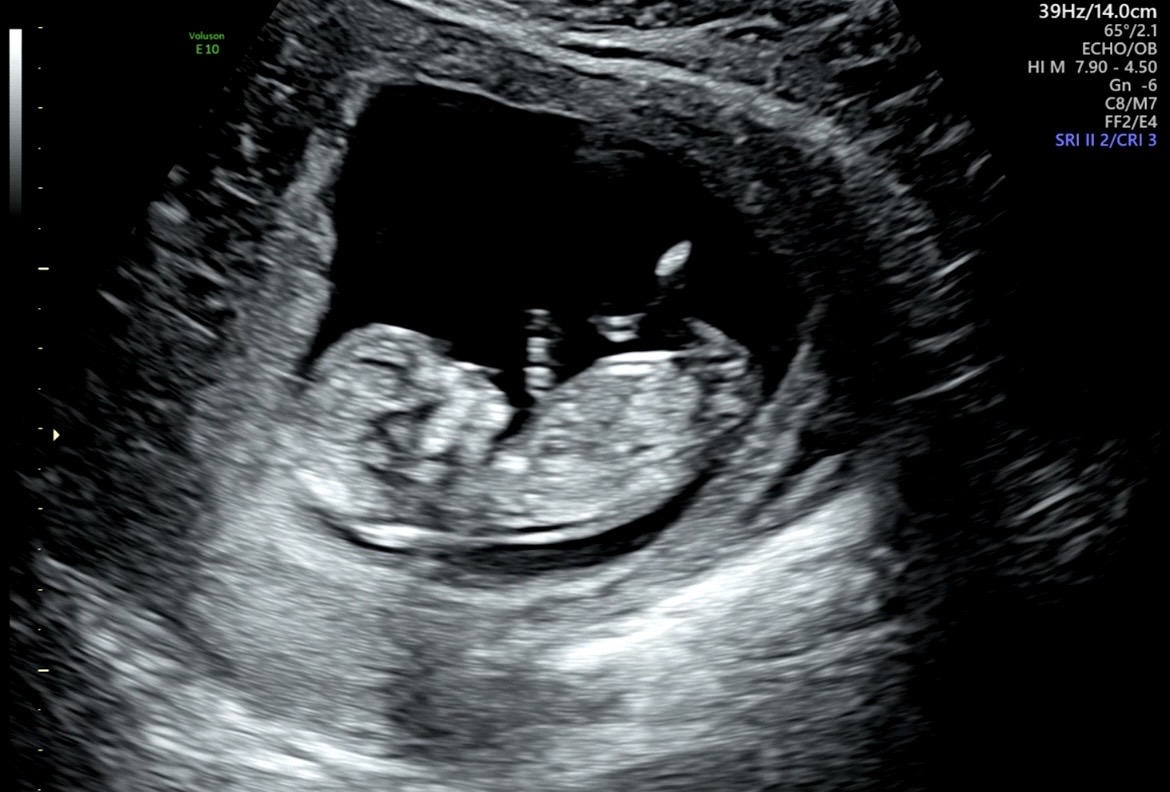

12주차 아들, 딸 너무 궁금해요. 도와주세요!

12주 1일차 입니다! 투표부탁드려요🙏